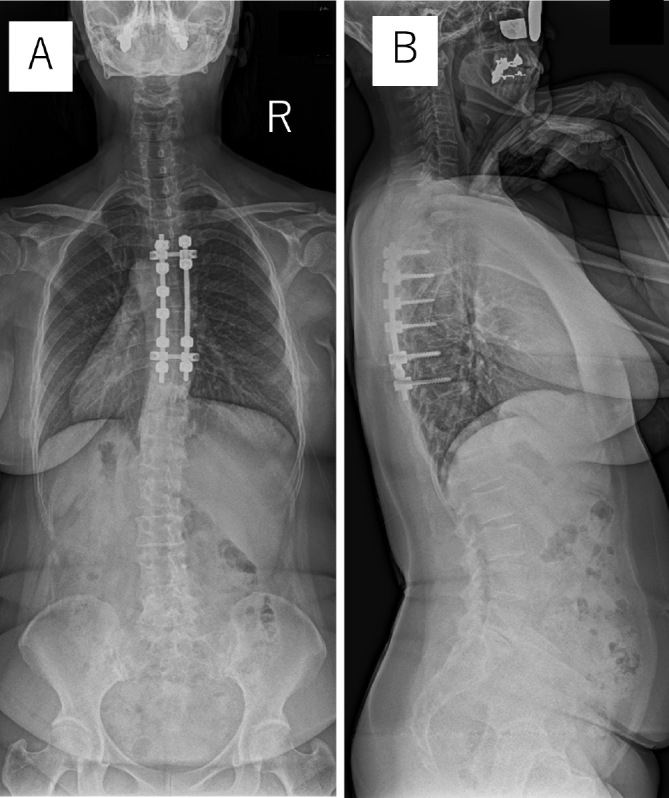

A Case of an Iatrogenic Pseudomeningocele after Thoracic Spinal Cord Tumor Surgery with a Long-Term Follow-Up.

一例胸椎脊髓肿瘤手术后的先天性假性脊髓膜膨出症及长期随访。